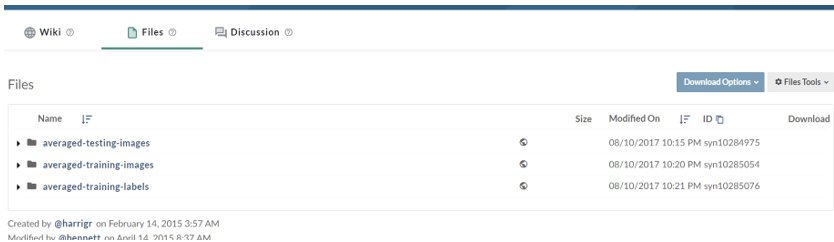

然后,如下图所示,选择下载文件进行下载,我们可以看到,数据分为训练(training)、标签(label)、测试(test)三种,这里介绍下,一般分割比赛是将训练数据集以一定比例划分为训练集和开发集,训练集训练网络,开发集简单验证泛化性能,而官方给出的测试集则是对每位选手赋分的依据,不提供GD,因此,这里我们选择下载前两者数据文件,点击后会提示注册,按照指引注册即可。